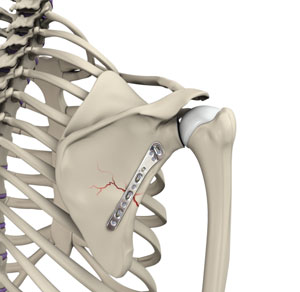

• ORIF of the Scapula Fractures

Img-ORIF of the Scapula Fractures

The scapula (shoulder blade) is a flat, triangular bone providing attachment to the muscles of the back...